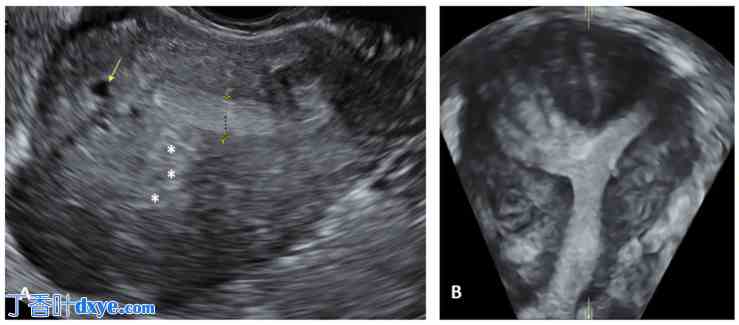

图 2.

深部浸润型子宫内膜异位症 (DIE) 的经阴道超声 (TVS) 表现。(A) 子宫骶韧带 (USL) 低回声结节(黄色虚线);(B) 累及直肠和子宫圆环(POD:Douglas 袋)的 DIE 低回声结节;(C) 直肠子宫内膜异位症结节(黄色虚线)及其相关的 USL 结节(黄色箭头); (D) 直肠子宫内膜异位症结节(黄色箭头)。